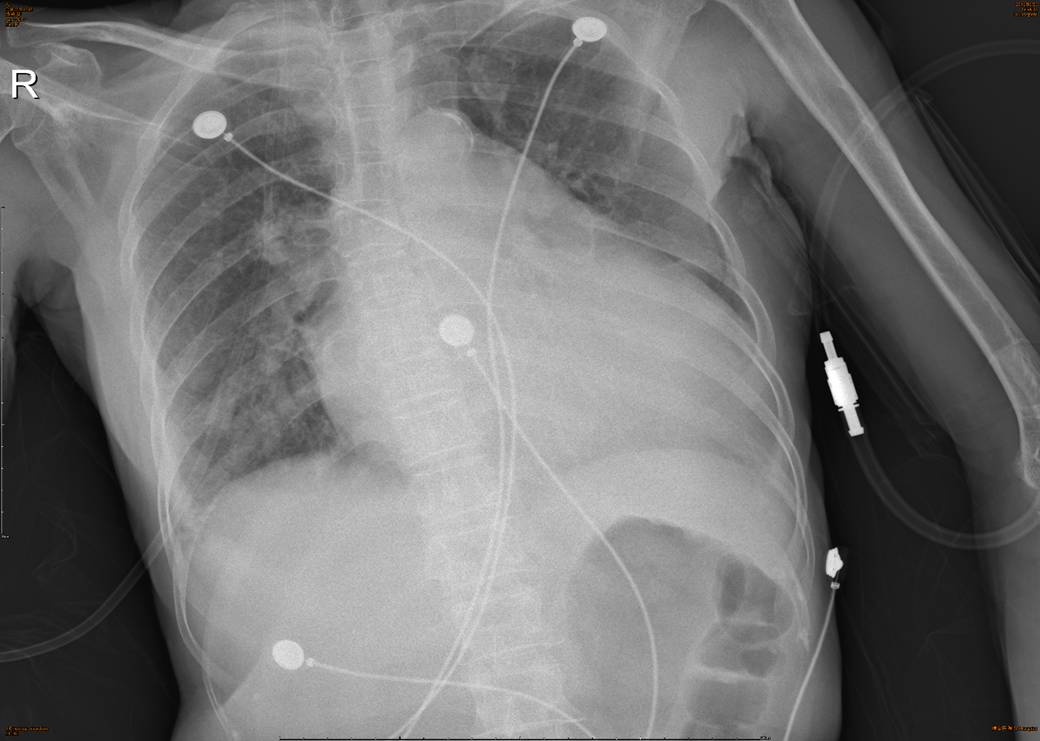

【胸片】:

影像描述: 所示胸廓骨骼及胸壁软组织未见异常。纵隔及气管居中未见移位。

纵隔未见增宽。

心影明显增大,主动脉壁钙化。

两膈光整,右肋膈角欠清,左肋膈角变钝。

两侧肺门影增大模糊。

两下肺纹理增多,两下肺斑片状模糊影。

诊断意见:心影明显增大,主动脉壁钙化。两下肺渗出,两侧胸腔积液;两侧肺门影增大模糊。